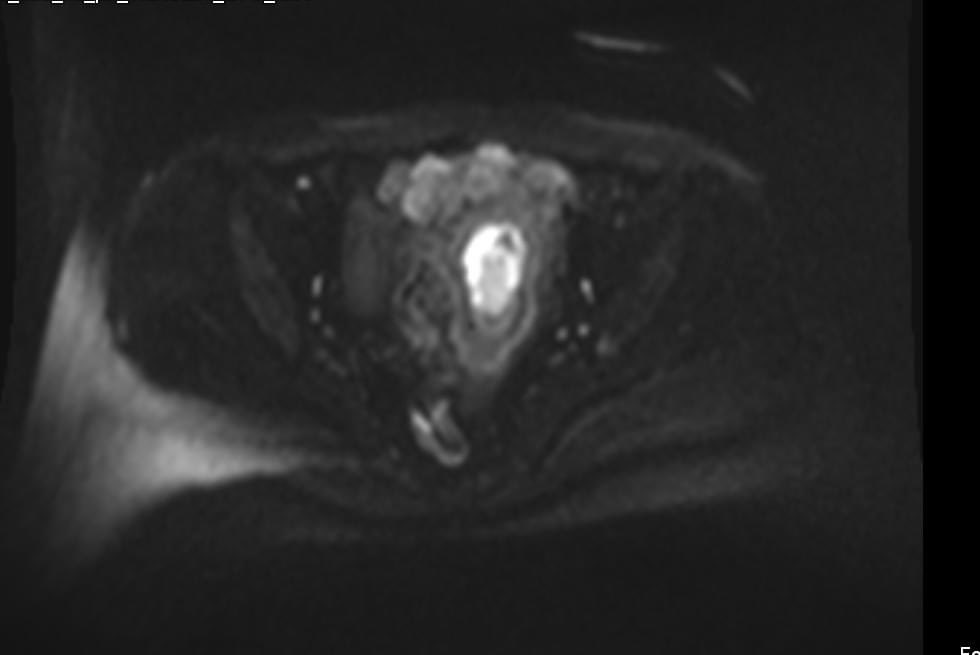

58-year-old female with active vaginal bleeding #Findings: •There is thickening of the endometrium measuring 14mm in thickness with internal intermediate signal intensity seen. •The lesion is seen extending into the myometrium with invasion of the serosa layers. •The lesion

hemo_shk's tweet image. 58-year-old female with active vaginal bleeding

#Findings:

•There is thickening of the endometrium measuring 14mm in thickness with internal intermediate signal intensity seen.

•The lesion is seen extending into the myometrium with invasion of the serosa layers.

•The lesion

- 58-year-old female with vaginal bleeding for the past 2 months - findings and diagnosis ? #MEDHM @IhabFathiSulima #MedEd #MedX

hemo_shk's tweet image. - 58-year-old female with vaginal bleeding for the past 2 months

- findings and diagnosis ?